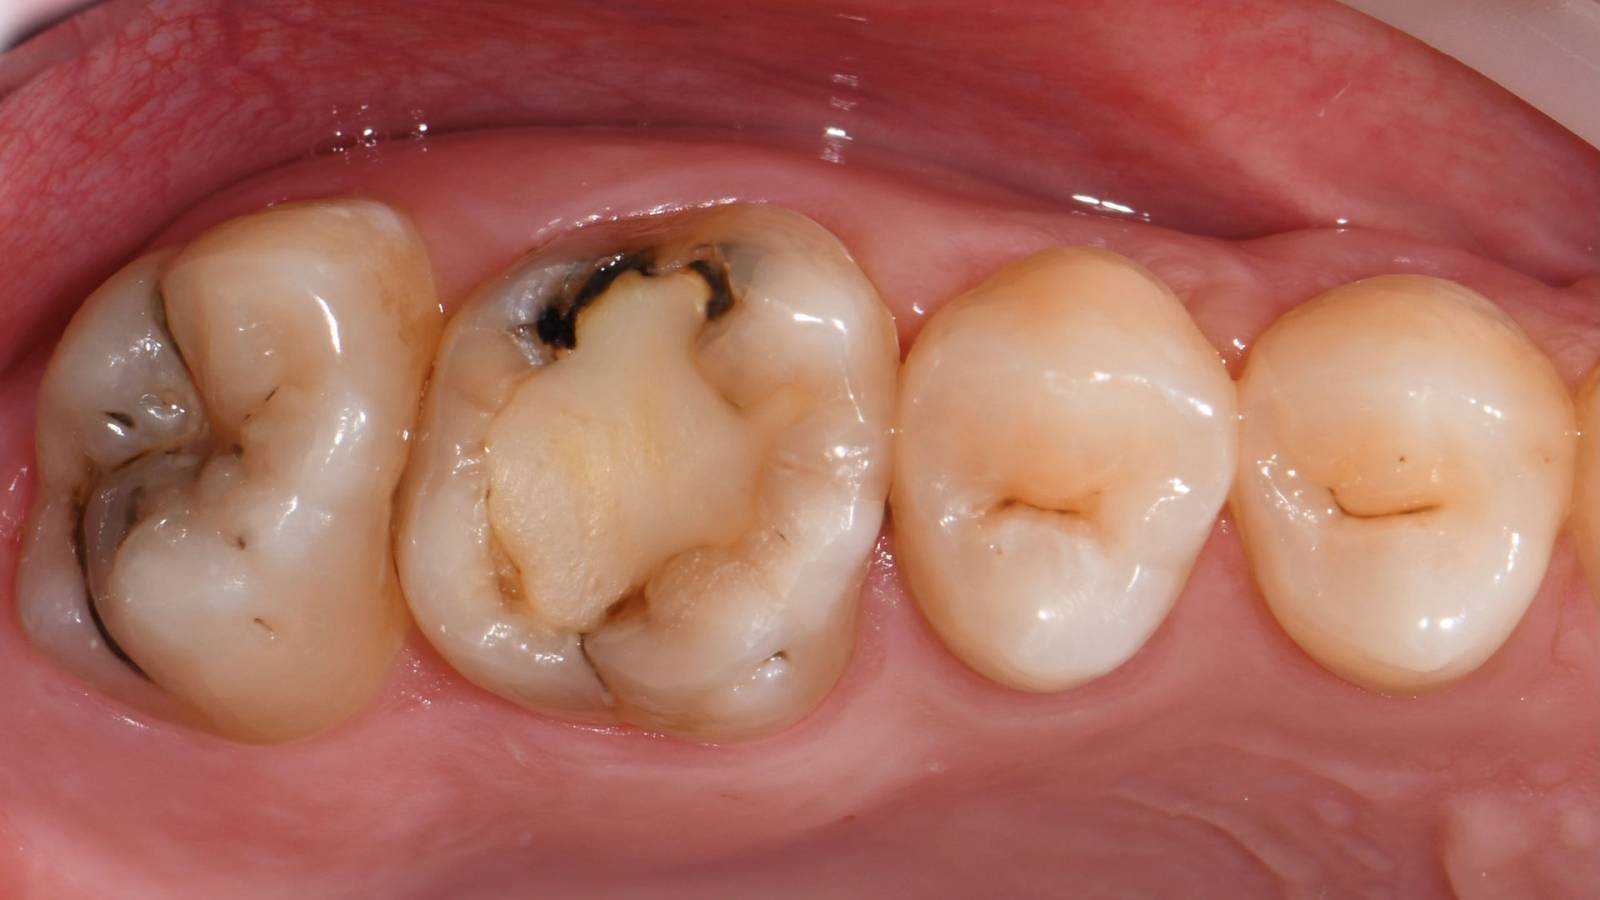

Lower second molar chairside restoration

A partial CEREC Tessera crown

A lower second molar with sensitivity presented with cracks as well as an extensive Class I composite restoration on the buccal surface. According to the minimally invasive concept a CAD/CAM partial crown was planned, fabricated and bonded using CEREC Tessera in a single visit.

Before: Failed amalgam restoration needing replacement. Patient complaining of sensitivity and tooth presenting multiple cracks.

After: Chairside CAD/CAM partial crown restoration fabricated with CEREC Tessera Advanced Lithium-Disilicate glass ceramic.

Dr. Carlos Eduardo Sabrosa

Rio de Janeiro, Brasil